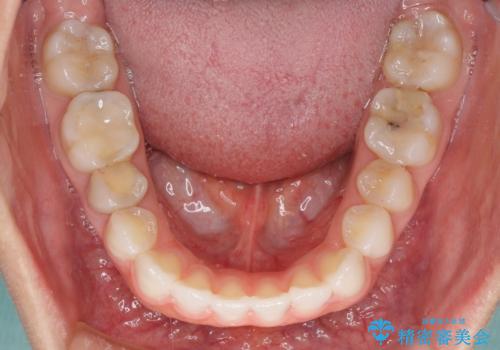

- 上下の前歯の反対咬合を気にして来院された患者様です。

インビザラインを用い、下顎はIPR(歯と歯の間を削る)と歯列全体を後方に移動させ、上顎は前歯を持ち上げることで、反対咬合を改善していくこととしました。

インビザラインによる反対咬合の改善は、上の歯が下の歯を乗り越えていく期間に咬み合わせが非常に不安定となり、治療が長期化することがあります。

こちらの患者様も、一時的に前歯でしか咬めない時期がありましたが、比較的早く咬み合わせが安定し、1年ほどで治療を終えることができました。